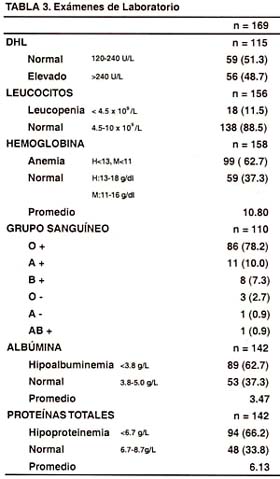

En la Tabla N° 3, se reporta los resultados de exámenes de laboratorio practicados en los 169 pacientes con Linfoma Gástrico. Hay que precisar que en cada acápite de los diferentes análisis se consigna el número de pacientes en quienes se realizaron los exámenes. Respecto al DHL, en los 115 pacientes a los cuales se les practicó dicho análisis, prácticamente la mitad tenía un DHL normal y la otra mitad un DHL elevado. Cuando se aprecia la cifra de leucocitos, la mayoría de los pacientes presentan cifras dentro del rango de normalidad respecto a la leucopenia (138/18). Las cifras de hemoglobina revelan anemia leve en 158 pacientes evaluados, con un promedio de 10.8 g/dl. El grupo sanguíneo predominante en 110 pacientes evaluados fue el O+ (78.2%), seguidos del A+ (10%), y del B+ (7.3%), siendo los otros grupos más bien infrecuentes. Cuando se analiza la presencia de hipoalbuminemia, en 142 pacientes estudiados al respecto, el 62.7% de los pacientes con Linfoma Gástrico presentan cifras bajas de albúmina, con un promedio de 3.47 g/L (rango normal de 3.8 – 5.0). De la misma manera, la hipoproteinemia se presentó en la mayoría de los pacientes (66.2%), con un promedio de 6.13 g/L (rango normal de 6.7 – 8.7).